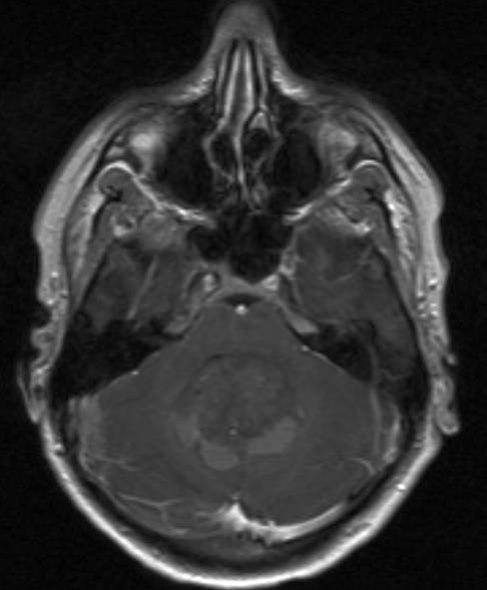

Medulloblastom, aksialt snitt

medulloblastom 1

Gjengitt med tillatelse av Radiologisk avdeling, Universitetssykehuset Nord-Norge